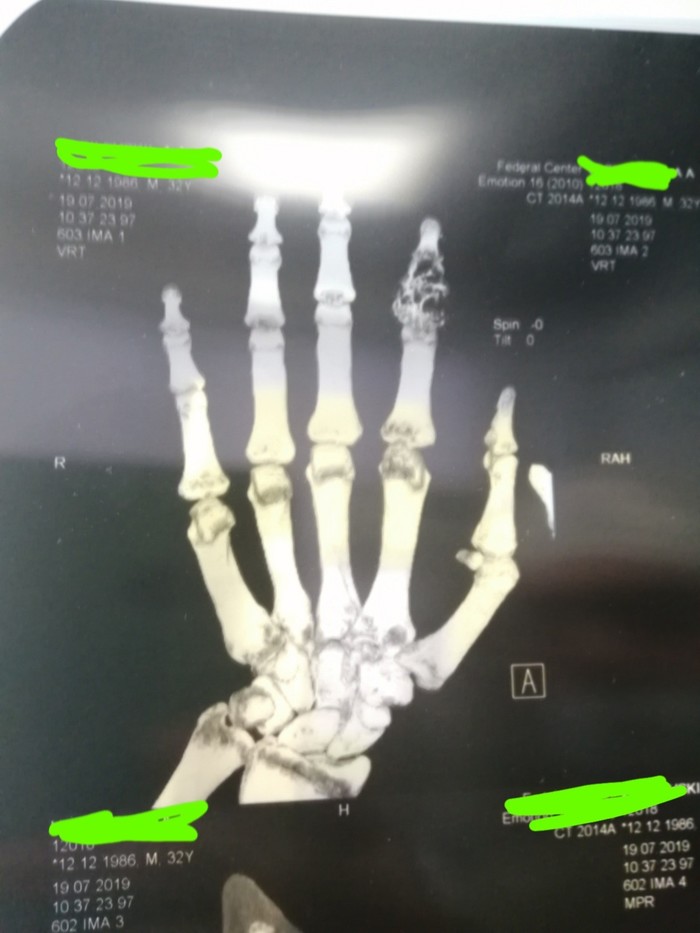

Экскохлеация энхондромы

Полтора года назад палец попал под работающую дрель. Лечился самостоятельно. Когда палец окончательно распух и движения стали ограничиваться, пришёл полечиться.

На рентген видно что в кости выросла хрящевая ткань.

Причины появления таких доброкачественных опухолей пока не выяснены. Но чаще случаются до 40 лет.